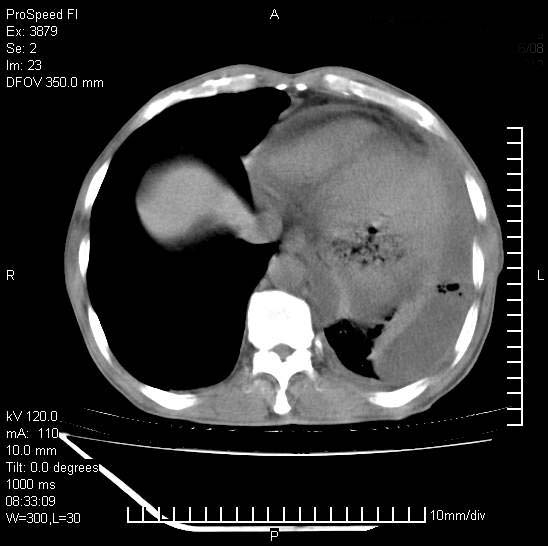

以下是引用37度在2008-6-6 11:20:00的发言:[br]1.包裹性积液,多考虑结核性;[br]2.穿刺术后改变。